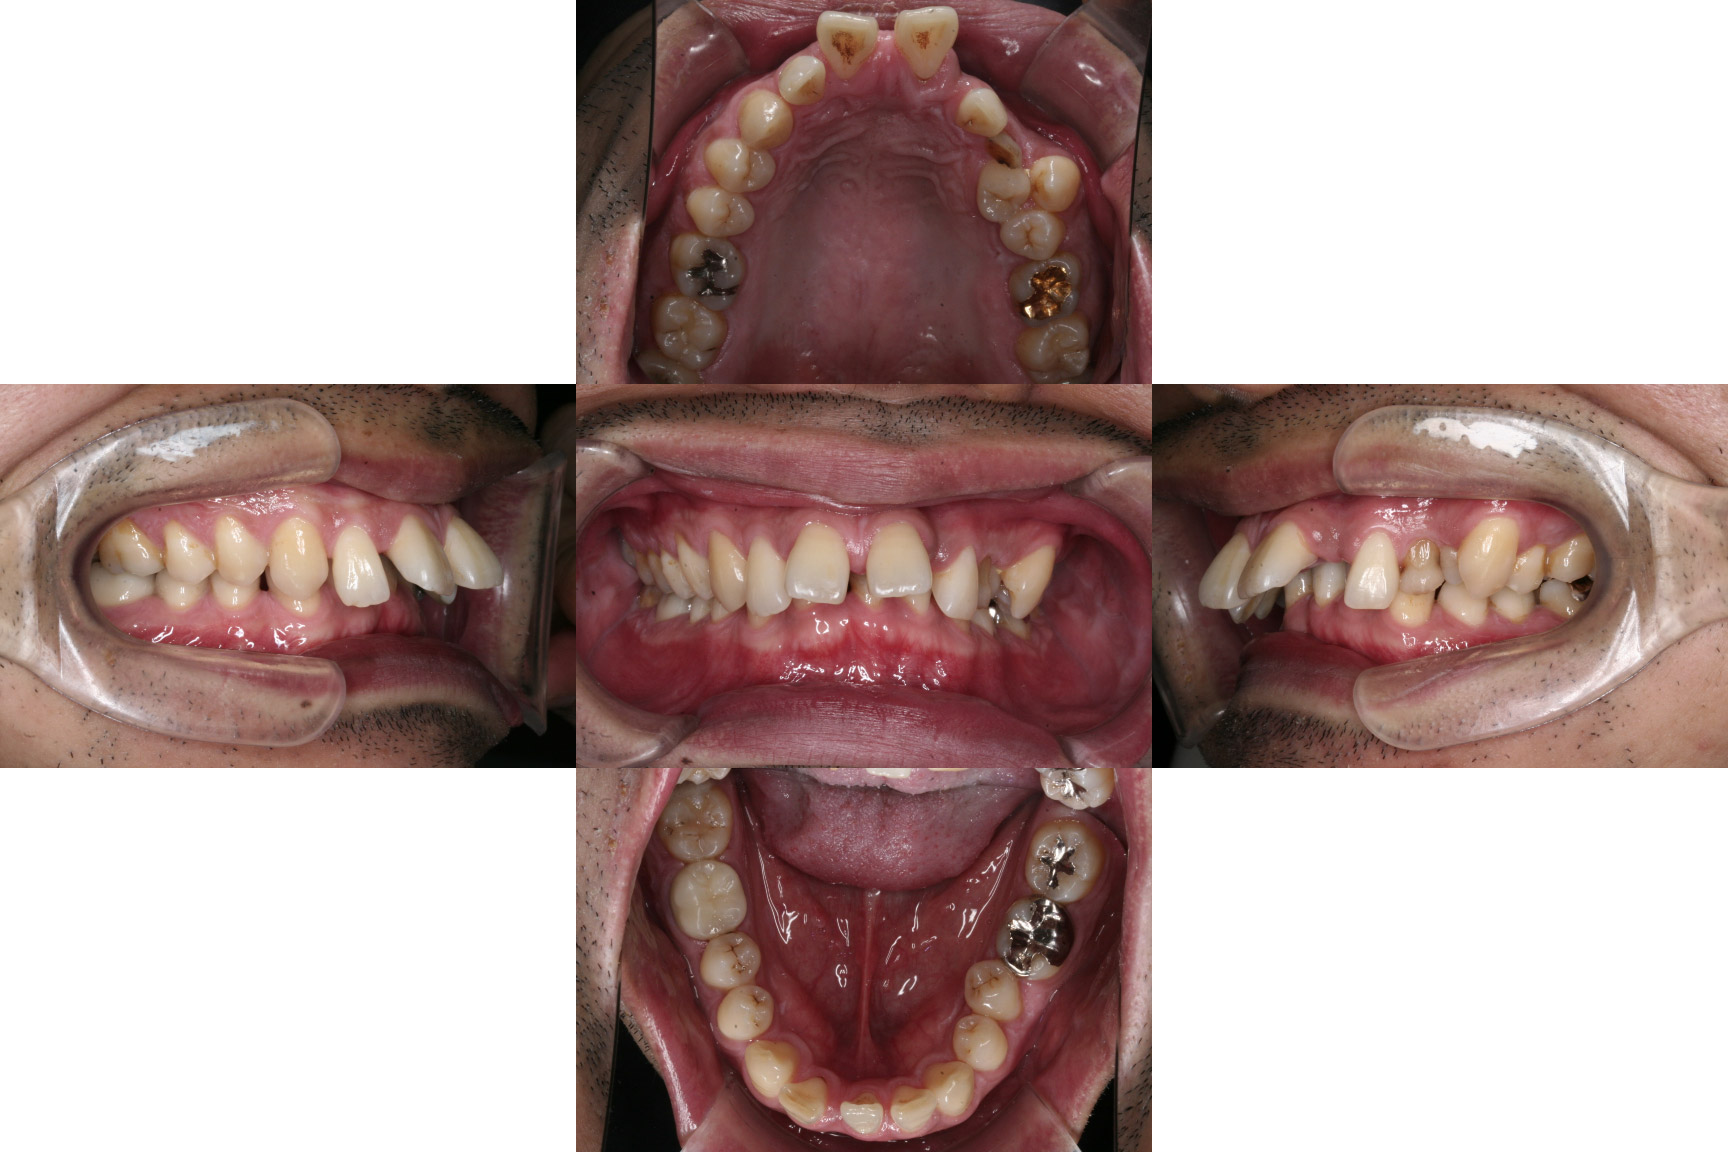

| 主訴 | 【主訴】ディープバイト,すきっ歯 【診断・症状】左上C残存、下顎右下1番欠損、上顎前突、空隙歯列、過蓋咬合 |